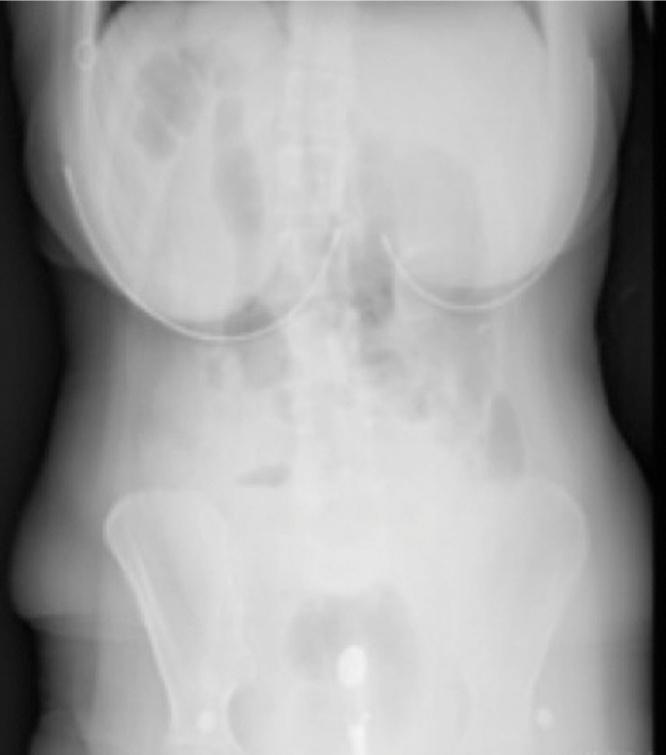

Meckel's diverticulum is a real diverticulum located at the antimesenteric portion of intestinal loops and including all layers of the intestinal wall. It is the most common congenital anomaly of the gastrointestinal tract, and its incidence is 1-3%. Many asymptomatic cases are diagnosed when complications occur. A 23-year-old female patient applied to gynaecology emergency clinic with pelvic pain complaint. Laparotomy was performed with the diagnosis of acute abdomen because the physical examination and imaging studies did not exclude tuboovary pathology. Giant Meckel's diverticulitis and ischemic bowel loops that had been torsion were observed. Obstruction is the most common complication and generally originates from inflammation, adhesions, intussusception and omphalo-mesenteric band. In this case, it was seen that mobilized diverticulitis can be complicated without any fibrous band or adhesion to adjacent organs. This case supports that there can be torsion of bowel in free Meckel's diverticulum. Meckel's diverticulum settled in the pelvic region can make a clinical manifestation that is difficult to distinguish from adnexal diseases. It should be kept in mind for cases that start with pelvic pain, form adnexal pathology suspicion and cause an acute abdomen.

梅克尔憩室是位于肠袢肠系膜对侧部分的真性憩室,包含肠壁各层。它是胃肠道最常见的先天性异常,发病率为1% - 3%。许多无症状病例在出现并发症时才被诊断出来。一名23岁女性患者因盆腔疼痛主诉前往妇科急诊就诊。由于体格检查和影像学检查未排除输卵管卵巢病变,故以急腹症诊断行剖腹手术。术中观察到巨大梅克尔憩室炎和扭转的缺血性肠袢。梗阻是最常见的并发症,通常源于炎症、粘连、肠套叠和脐肠系膜带。在本病例中,可见游离的憩室炎可在无任何纤维带或与相邻器官粘连的情况下发生并发症。该病例支持游离的梅克尔憩室内肠管可发生扭转。位于盆腔区域的梅克尔憩室可产生难以与附件疾病相鉴别的临床表现。对于以盆腔疼痛起病、形成附件病变怀疑并导致急腹症的病例应予以考虑。